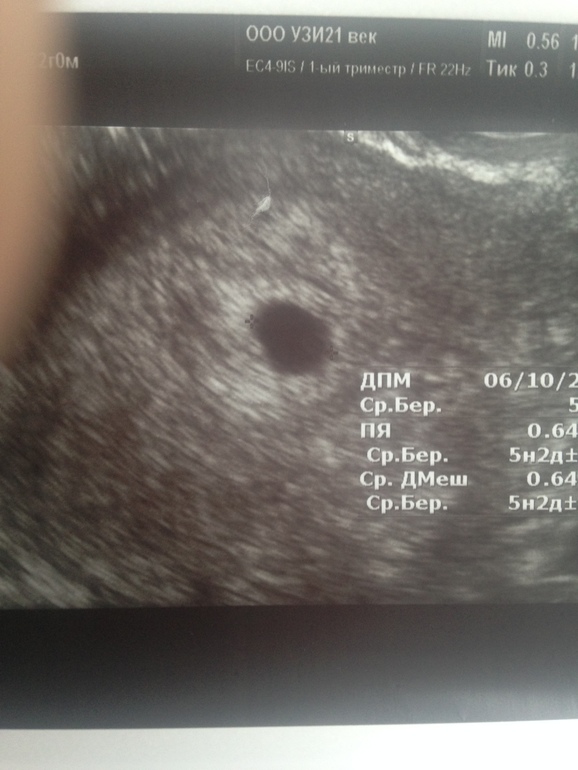

УЗИ, КТГ, доплервсем хорошего дня и самочувствия💋Нам 5,5 недель акушерских )История загадочная про беременность,позже напишу пост,когда услышу заветный звук сердечка!А сейчас меня интересует вот что Была я на УЗИ вчера(рекомендация врача) ,сказали все соответсвует сроку,через 10 дней контроль эмбриончика и СБ,ну а пока только ПЯ 6*7мм))Спросила про ЖМ,мне узист сказал,что он с эмбрионом появится,но на снимке я вижу его)хах)может и бред,но посмотрите,кто нибудь кроме меня видит кружочек?))я уже все фильтры освоила,ну просто Иниересно и не более того))фото воть